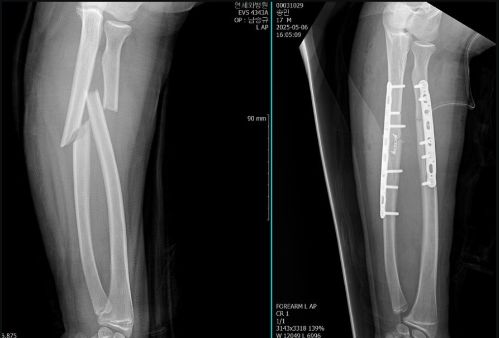

공개된 사진에는 민이의 팔 뼈 골절 전후 엑스레이와 수술 후 모습이 담겼다. 한 장의 엑스레이 사진에서는 팔뼈가 완전히 부러진 모습이, 다른 사진에서는 철심과 플레이트로 단단히 고정된 모습이 포착됐다.

병원 침대에 앉은 민이는 팔 보호대를 착용한 채 미소를 짓고 있었고, 또 다른 사진에서는 회복 중인 모습으로 아이스크림을 먹으며 엄마 오윤아와 함께 여유를 즐기는 모습이 담겼다.